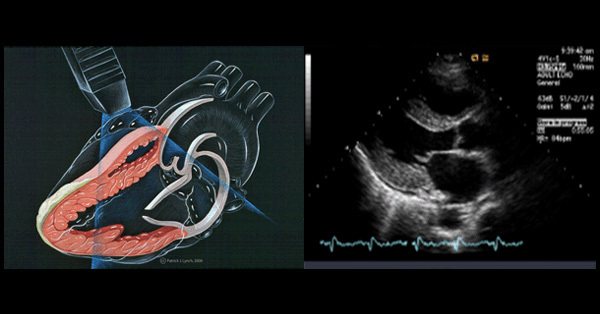

| 심장 판막의 평가 | 심장내의 판막의 형태와 혈류역학적인 정보를 알 수 있어, 초음파 검사만으로도판막 질환의 원인과 심한 정도를 평가 할 수 있다. |

흉골연(parasternal), 심첨부(apical), 늑골하부(subcostal), 흉골상부(suprasternal)이다. 흉골연에서는 좌심실, 좌심방, 대동맥의 내경과 좌심실벽 두께, 좌심실 박출계수 등을 측정한다.

1) 후천성 판막질환

(1) 승모판 협착증 : 승모판이 두껍고 움직임이 저하되고 개구면적 감소, 승모판 혈류속도 증가, 폐정맥과 폐동맥 고혈압 유발

(2) 승포판 폐쇄부전증 : 승모판이 두껍고 탈출 등에 의한 장애가 나타난다. 수축기에 좌심방으로 고속의 혈류가 역류 관찰된다.

(3) 동맥판 협착증 : 대동맥 판막의 비후, 석회화 및 운동저하가 관찰되며 대동맥판 혈류속도 증가 관찰된다.

(4) 대동맥판 폐쇄부전증 : 좌심실 용적과부하, 확장기에 대동맥에서 좌심실로 고속의혈류가 역류가 관찰된다.

(5) 삼첨판 폐쇄부전증 : 우심방 비대, 우심방으로 수축기 역류

(6) 감염성 심내막염 : 우종(vegetation)의 발견